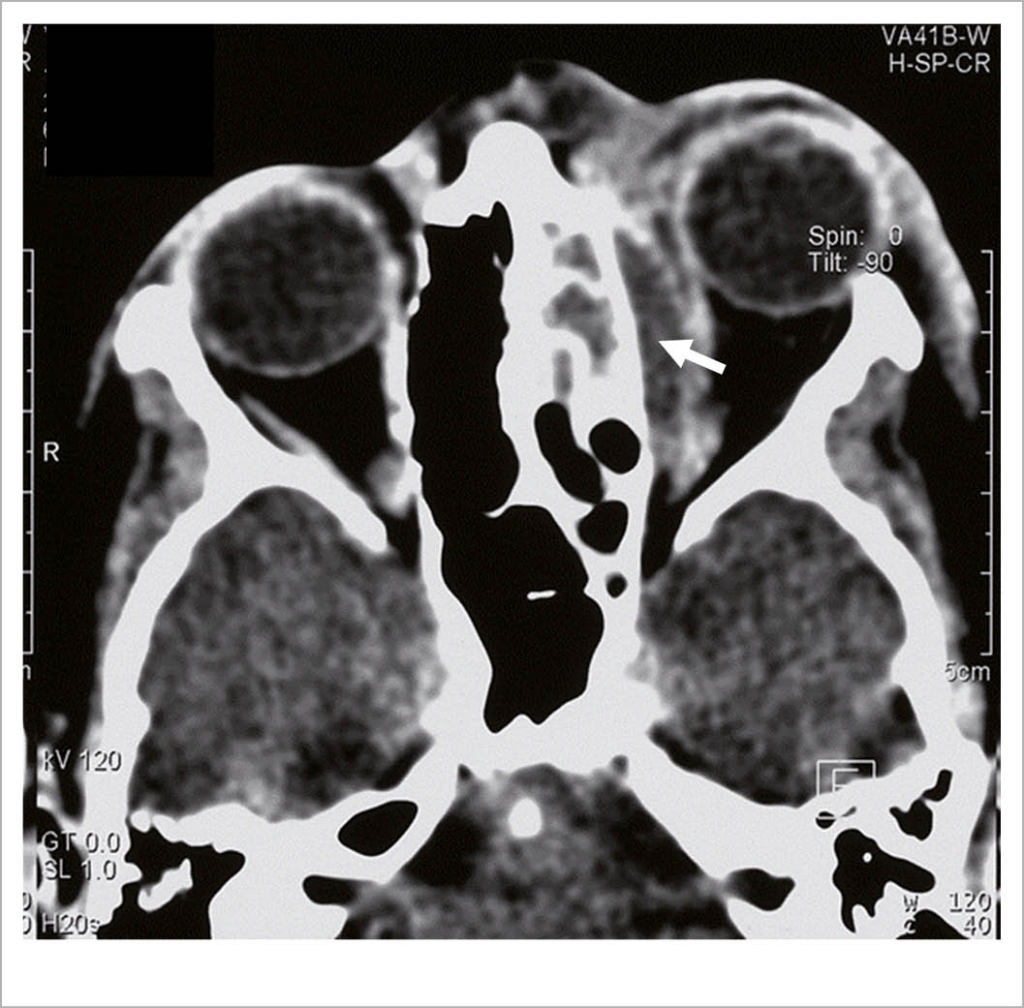

Unser Kind kann jedoch sein Auge nicht mehr aktiv öffnen und hat schmerzhafte Augenbewegungen, was für eine relevante orbitale Komplikation spricht. Und so zeigt die weitere notfallmässige Abklärung im Spital in der Computertomographie einen grossen Subperiostalabszess in der linken Orbita (Abb. 2). Der Abszess wird operativ entlastet und antibiotisch behandelt. Eine bleibende Schädigung des Auges kann vermieden werden.

Kindesalter treten vor allem orbitale Komplikationen auf, welche von den Sinus ethmoidales ausgehen. Dabei wandern die Bakterien durch die Lamina papyracea hindurch in die Orbita. Anschliessend bildet sich durch Abhebung der Periorbita der Subperiostalabszess aus. Unbehandelt können orbitale Komplikationen zu einer Erblindung oder zu einem lebensbedrohlichen aufsteigenden Infekt mit Sinus cavernosus-Thrombose und Meningitis führen.